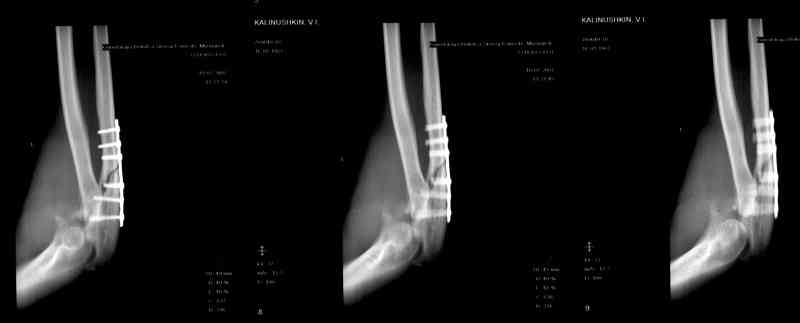

Естественно ревизия сустава и удаление рубцово-хрящевидных тканей.Затем наложили аппарат Илизарова с шарнирами. Первые 2 дня сустав был фиксирован трансартикулярно 2-мя спицами, затем спицы удалили. И больной начинает движения в аппарате.

Прилагаюся послеоперационные рентгенограммы.

Планиуем аппарат на 3-4 нед.

Что-то по снимкам ось шарниров с осью вращения локтевого сустава не сильно близко.

В аппарате Илизарова пытаемся сохранить объем движений, что и до операции, но хотелось бы увеличить. Поэтому начали ранние движения в локтевом суставе.